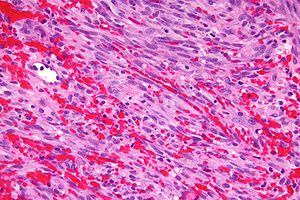

Microscopic

- No light microscopic changes.